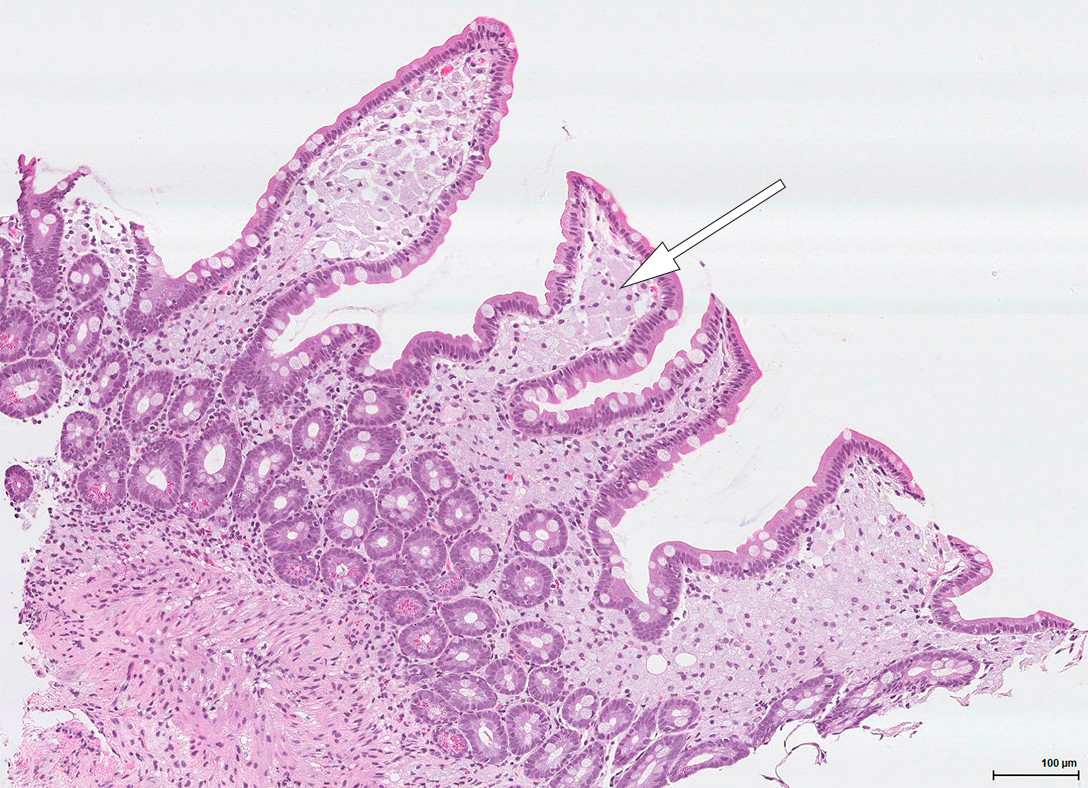

Konstellasjonen av migrerende leddsmerter og synovitter over flere år uten utvikling av radiologiske artrittforandringer, kombinert med intermitterende diaré og proteintapende enteropati gjorde at vi mistenkte Whipples sykdom, en sjelden infeksjonssykdom forårsaket av den grampositive bakterien Tropheryma whipplei. Pasienten ble henvist til gastroskopi og kapselendoskopi av tynntarm som viste betydelig inflammasjon med erosjoner, hemoragiske slimhinner og diffus lymfangiektasi (fig 2) (fig 3). Duodenalbiopsier viste breddeøkte totter og akkumulering av skummakrofager med periodisk syre-Schiff (PAS) diastasepositive granulære inklusjoner i cytoplasma (fig 4) (fig 5). Både de makroskopiske og histopatologiske funnene var godt forenlig med Whipples sykdom. PCR utført etter DNA-ekstraksjon fra parafininnstøpt tarmbiopsi var positiv for T. whipplei for to separate målgener (varmesjokkprotein og 16S rRNA). Sekvensering av 16S rDNA PCR-produktet bekreftet T. whipplei. Pasientens ikke-destruktive seronegative artritt, diaré, malabsorpsjon og utmattelse ble antatt å representere manifestasjoner av Whipples sykdom. Iskemiske slag og lungeembolier er beskrevet hos pasienter med Whipples sykdom, og sykdommen representerte en plausibel årsak til pasientens hittil uforklarlige trombosetendens (1),( 2).

Klassisk Whipples sykdom diagnostiseres på bakgrunn av øvre endoskopi, duodenalbiopsier og PCR-undersøkelse. Gastroskopi kan vise ødematøse slimhinner med erosjoner og lymfangiektasi. Lymfangiektasien skyldes akkumulering av makrofager i lymfekarene, med resulterende lymfestase. Allikevel er det viktig å være klar over at de fleste pasientene har makroskopisk normal tynntarmsslimhinne, så biopsier anbefales selv ved upåfallende gastroskopi (5). Multiple biopsier øker sensitiviteten (6). Kapselendoskopi av tynntarm kan brukes for å kartlegge sykdomsutbredelsen. Mikroskopering av duodenalbiopsi viser akkumulering av skummakrofager med PAS-positive intracellulære inklusjoner. Det PAS-diastase-positive materialet svarer til bakteriekapselen som inneholder mykopolysakkarider. Andre årsaker til PAS-positive makrofagansamlinger i tynntarm er blant annet mykobakterieinfeksjon, avleiringssykdommer og langerhanscelle-histiocytose. Disse differensialdiagnosene kan avkreftes med tilleggsundersøkelser.